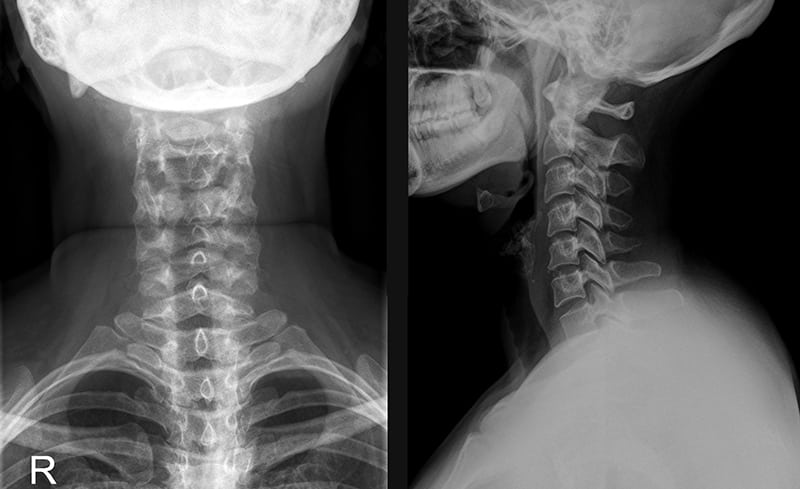

Для выявления степени повреждения могут использоваться рентгенография, УЗИ, КТ. Наиболее информативная диагностическая методика — магнитно-резонансная томография. В терапии применяются консервативные способы: ношение ортопедических воротников, физиопроцедуры, ЛФК, нанесение на область шеи мазей от растяжений с анальгетическим и противовоспалительным действием.